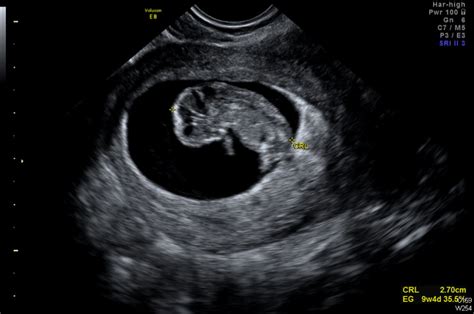

Ecografía Obstétrica del Primer Trimestre

La ecografía del primer trimestre, realizada entre las semanas 11 y 14 de gestación, es una de las más importantes. Permite comprobar el estado del embrión, calcular la edad gestacional y detectar posibles anomalías en el desarrollo fetal. Una ecografía obstétrica preliminar puede realizarse entre las semanas 7 y 8 para confirmar la implantación, verificar el latido cardíaco y determinar el número exacto de embriones.

La primera consulta médica suele realizarse entre la semana 6 y 8, contando desde el primer día de la última regla. En esta visita se lleva a cabo la primera ecografía con los siguientes objetivos:

- Esbrinar si la gestación es evolutiva.

- Precisar la localización intrauterina del saco gestacional.

- Calcular ecográficamente las semanas de gestación.

- Conocer el número de embriones.

- Aclarar si existe alguna patología asociada (quistes ováricos, miomas).